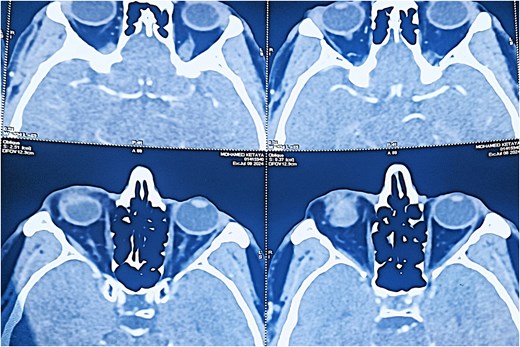

Angio-computed tomography (CT) imaging revealed a well-circumscribed mass measuring 22 × 24 × 18 mm with peripheral contrast enhancement, consistent with a vascularized lesion. Magnetic resonance imaging (MRI) was not performed due to financial limitations. The lesion did not show signs of invasion into adjacent structures (Figs 3 and 4).

Axial CT scan (soft tissue window) revealing a well-defined, ovoid lesion with peripheral contrast enhancement in the inferior orbital region.

Coronal CT scan showing the subcutaneous location of the tumor with no invasion of adjacent structures.

Radiologically, the angio-CT revealed a well-circumscribed mass measuring 22 × 24 × 18 mm with peripheral contrast enhancement, typical for vascular tumors [4]. This peripheral pattern likely corresponds to the rich vascular capsule and differentiates it from other lesions exhibiting homogeneous enhancement. Unfortunately, MRI was not available for this patient due to economic constraints, representing a limitation of this report. MRI would have allowed better tissue characterization and vascular mapping, aiding preoperative planning [5].

The discrepancy between the clinical (15 mm), histopathological (15 × 10 mm), and imaging (22 × 24 × 18 mm) tumor sizes can be attributed to the peritumoral vascular and connective tissue extension captured by imaging modalities but not measured clinically or histologically. This is consistent with vascular tumor behavior, where the radiological extent may exceed the gross tumor size [6].